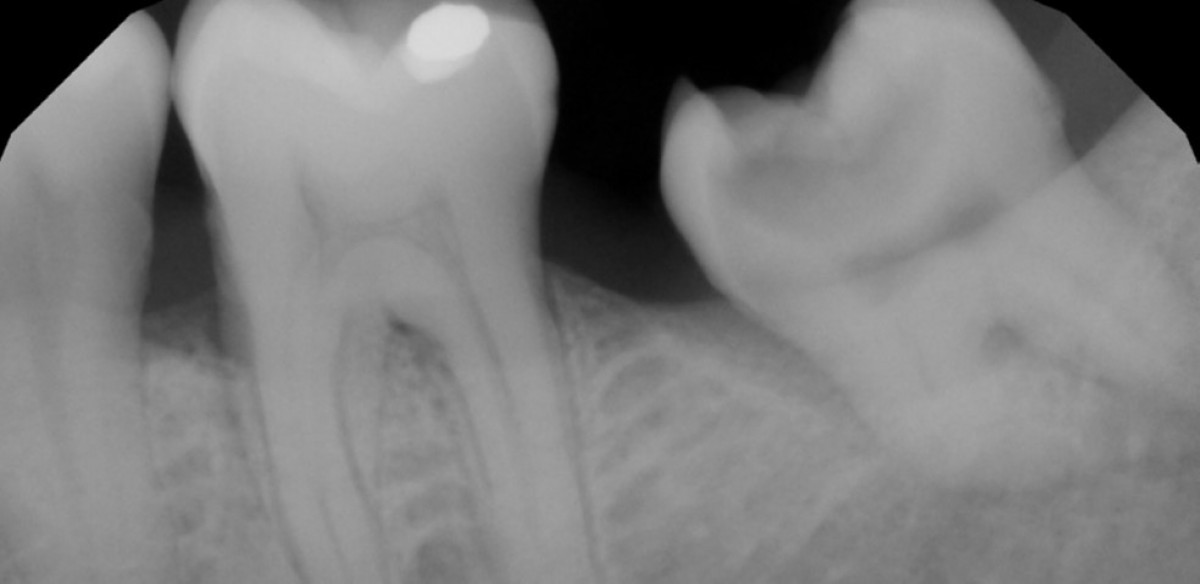

A 40 years-old patient was referred to our clinic for endodontic retreatment: the patient felt pain while chewing on a lower right first molar. The pre-operative x-ray showed that the root canal lumen was visibly diminished and the pulp chamber had been filled with flowable composite (Fig. 1), while the clinical exam showed a large and abraded composite restoration.